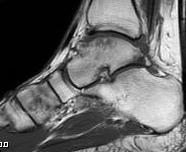

Subluxation of TNJ with advanced STJ OA

TNJ OA with posterior / medial / anterior facet OA of the subtalar joint

Union

Nonunion

Ankle joint arthritis

Ebalard et al Orthop Traumatol Surg Res 2014

- 72 hind and midfoot fusions with minimum 10 year follow up

- 73% tibiotalar arthritis